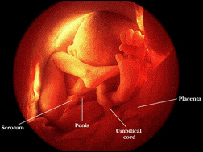

معمولا مرحله رشد وتکميل بدن جنين دربطن مادر40 و گاهی هم 36 هفته يا کم وبيش را در بر می گيرد. مسوولين شفاخانه ملالی از مريضانی گفته اند که از تاخير ولادت دچار مشکلات شده اند. خانمی از همين بابت دوطفل مرده بدنيا آورد. دقت در تعيين وقت دقيق ازمسايل مهميست که داکترنيلوفرسلطانی ترينرمتخصص امراض نسايی بر آن تاکيد می کند. مادری ازکم شدن حرکات کودک دربطنش نگران بود، داکترنجم السما، کم شدن مايع شنای کودک را عامل اين مشکل می داند. همچنان سخت شدن پلاسنتا( جوره) بعد از 40 هفته تاخير در ولادت باعث رقيق شدن مايع شده جنين را تهديد می کند. بايد درسه ماه اول بارداری خانم ها نزد داکترمراجعه کنند تا به کمک داکتر وقت ولادت شان را دقيق ياداشت کنند. معاينات التراسوند درسه ماه اول بارداری می تواند برای تعيين وقت دقيق زايمان موثرباشد و سه ماه اخير نمی تواند تاريخ دقيق را برای خانم ها نشان دهد.

تعدادی از خانم ها ماه و روز ولادت شان را طبق ماه قمری (مهتابی) ويا هم آخرين روزعادت ماهوارشان تعيين می کنند. به باور داکترنجم السما، برای تعيين وقت ولادت، خوبترين شيوه آخرين تاريخ روزعادت ماهواراست. مادرانی که چنين کار را فراموش کرده حمل گرفتهاند تا سه ماه اول بارداری شان بايد نزد داکترمراجعه کنند و ازمشوره های لازم در زمينه مستفيد شوند. |